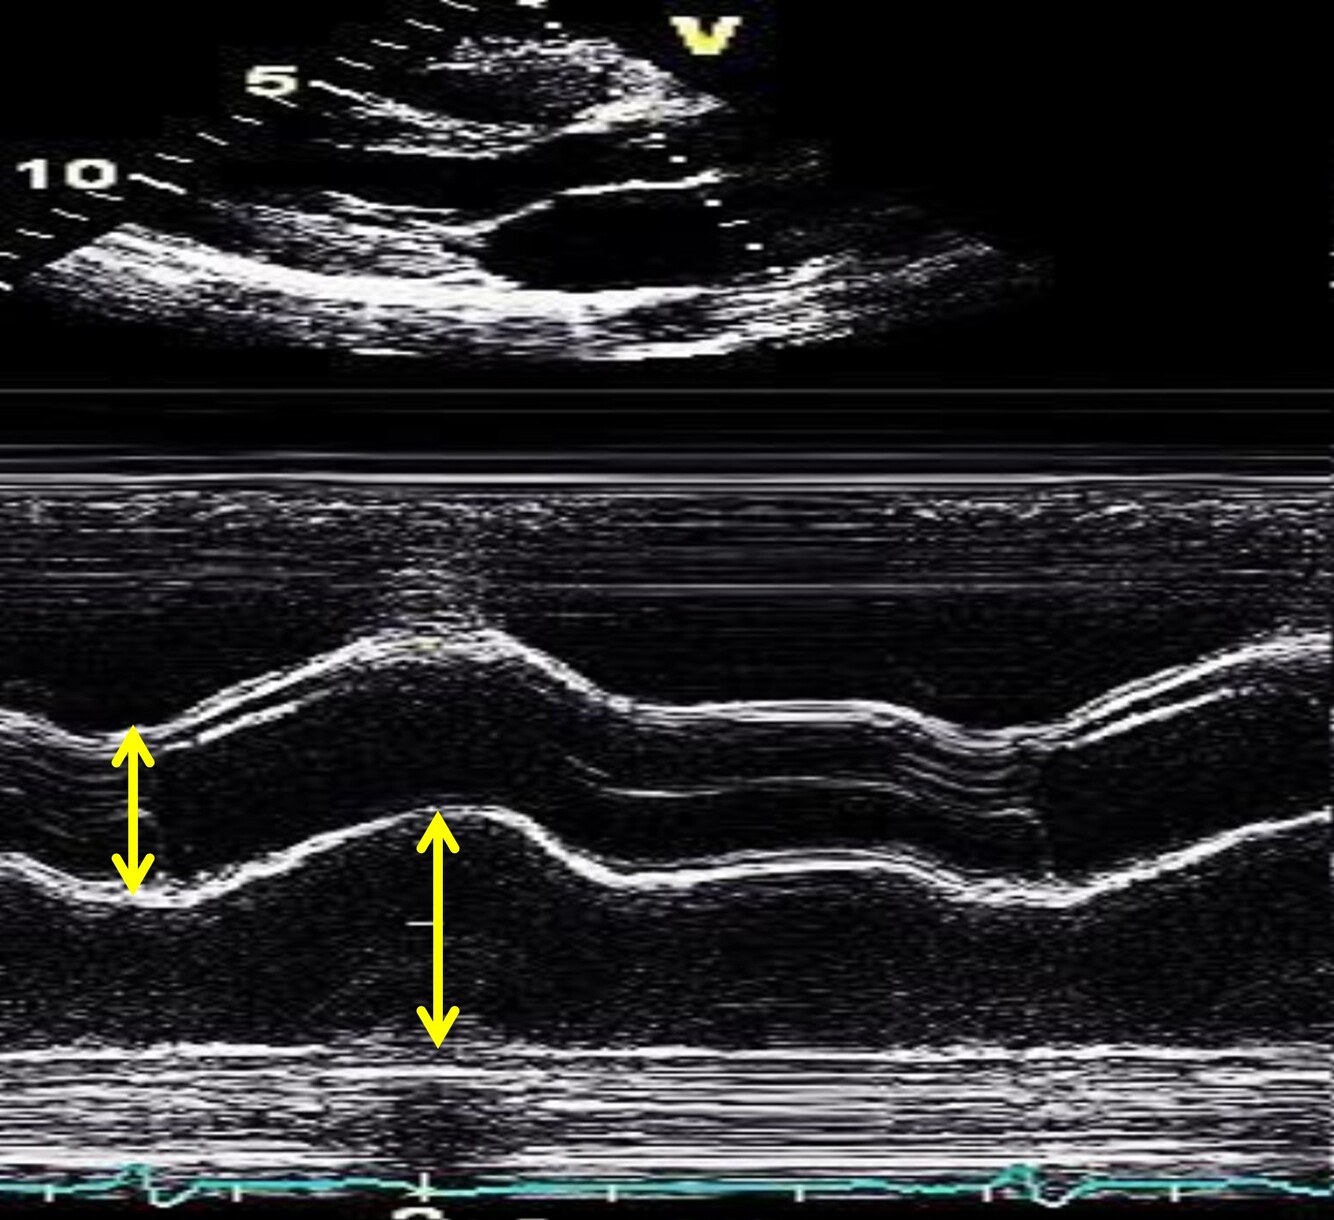

Label the M-mode image of the LV

1. RV 2. LV 3. ED 4. ES

Label the M-mode image of the LV from top to bottom

1. RV Ant. Wall 2. Septum 3. Post LV wall 4. Pericardium

34

What are the M-mode measurements for LV Diastole? 3

1. IVSd 2. LVIDd 3. LVPWd

35

What part of the ECG do we take the diastolic measures for LV M-mode?

QRS

36

What Systole M-mode measurements for LV do we take?

LVIDs

37

What are some tips to get the measurements for LVIDs?

Measure when the LV is at its smallest

38

How should we measure the IVSd for LV M-mode?

RV side of the LV septum to LV cavity

39

How should we measure the LVIDd for LV M-mode?

Posterior IVS to the posterior wall

40

How should we measure the LVPWd for LV M-mode?

LV cavity to the epicardium